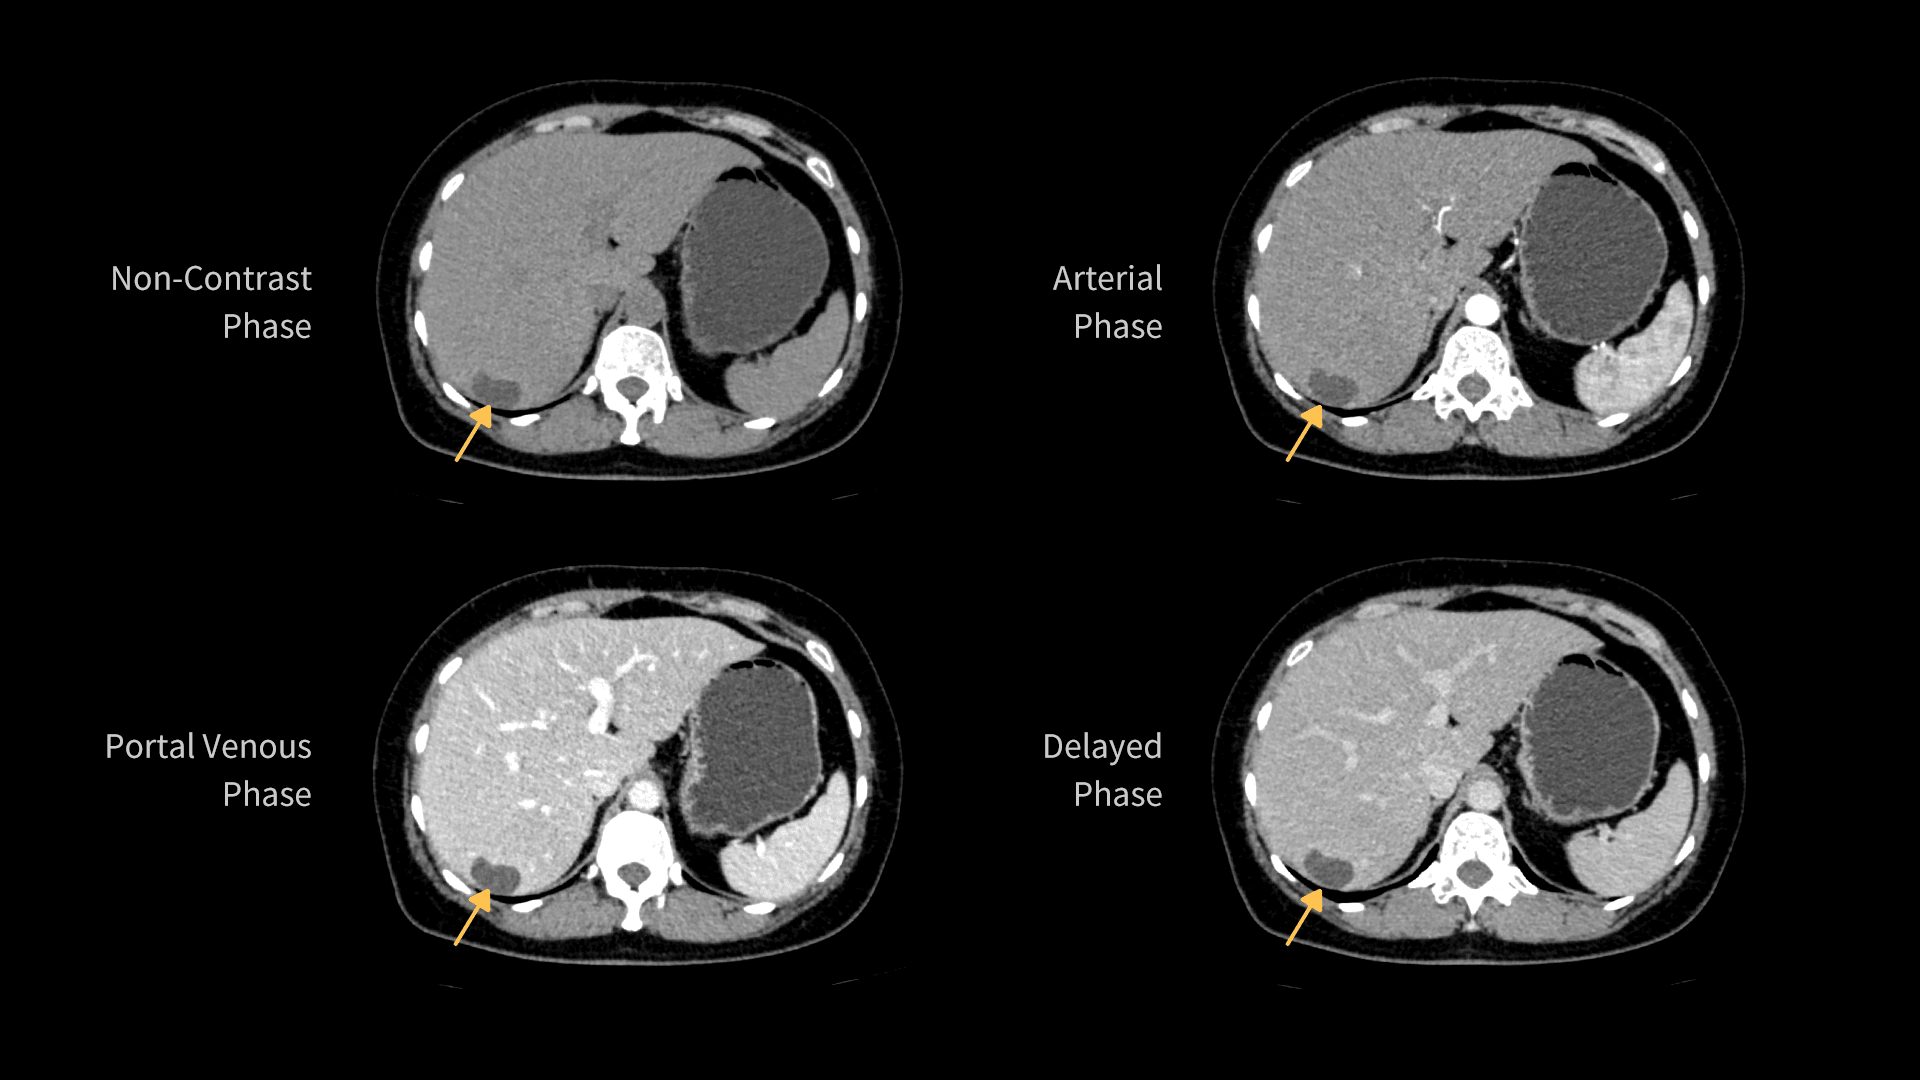

Imagistică Hepatică cu Contrast Multiphasic

uCT Orion Extra este echipat cu un detector Z de 40 de secțiuni, cu design inovator al chip-ului, care reduce nivelul de zgomot electronic. Această optimizare scade zgomotul în imaginile abdominale și îmbunătățește vizibilitatea limitelor leziunilor.

| Parametri scanare |

Timp rotație: 0.71 s / rotație kV: 100 mAs: 103 CTDIvol: 6.0 mGy Doză efectivă: 2.0 mSv |

| Parametri reconstrucție |

Matrice: 512 × 512 Grosime secțiune: 2.0 × 1.0 mm HIR: B_VSOFT_B WW/WL: 300/40 |

| Contrast |

350 mgI/ml 80 ml 2.5 ml/s |